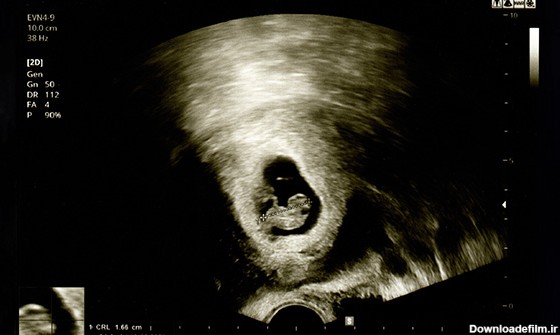

عکس جنین یک ونیم ماهه

اندازه جنین یک ماهه کوچکتر از یک دانه برنج است! اما در ماه اول بارداری خصوصیتهای ژنتیکی شکل میگیرد. آیا جنین یک ماهه جفت دارد؟ | عکس جنین یک ماهه در شکم مادر

در این مقاله در مورد تکامل اصلی جنین در هفته می خوانید و اندازه جنین مشخص میشود

رشد جنین یک ماهه، آنچه میخواهید بدانید و نی نی بان جنین در این زمان شبیه یک لوبیاست در این مقاله ابتدا تغییرات کلی جنین و بدن مادر و شکل جنین در ماه اول...